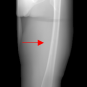

In this section, we provide qualitative and quantitative results of the two proposed diffusion-based methods and compare them with the baseline U-Net model. The first column of Fig. 3 showcases six randomly selected conditions: (a0)-(c0) show contour segmentations, and (d0)-(f0) denote segmentations containing contour and bones. In Fig. 3 (a1)-(f1), the images generated by U-Net contain blurred fine details in locations where bones overlap, despite maintaining the given shape, as highlighted by the red circle. In contrast, the results from CSM appear more realistic than the U-Net. However, their quality decreases with introduced constraints, as indicated by the red arrow in Fig. 3 (d2) and (f2). The results from CTM not only achieve nearly the same level of fineness as the labels but also provide reasonable results with respect to the given conditions as illustrated in the fourth column.

Table I summarizes the quantitative results averaged across all testing data. The evaluation metrics include mean absolute error (MAE) and peak signal-to-noise ratio (PSNR). We observed that CTM performs substantially better than U-Net and CSM under both segmentation-based conditions, and CSM performs worse than the U-Net.

Unlike the U-Net which learns a mapping function between input and output, the diffusion models can implicitly capture the underlying data distribution from the training data and then sample it, preventing the loss of fine details on the pixel level. However, in CSM, conditions are incorporated only at the first sampling step while being perturbed, which results in imprecise conditional information. Instead, CTM provides an estimated score function of the conditional distribution for each sampling step, accommodating both reliability and realism. Nonetheless, presently generated X-ray images only encompass independent 2D conditional information, which may introduce geometric inconsistencies between a set of projections. Future research will focus on modeling 3D probabilistic distributions with the provided 2D conditions to enable CT reconstruction from the generated projections. In addition, clinical datasets will also be incorporated.